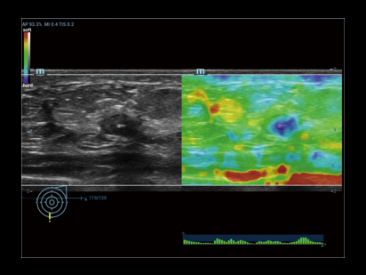

ElastografĂa de prĂłstata cualitativa por compresiĂłn y shear wave para dos mĂ©todos de biopsia diferentes.

ElastografĂa de prĂłstata: Carcinoma de prĂłstata

La nueva ElastografĂa Sound Touch (STE) permite tener una velocidad de cuadros mĂĄs alta en el campo, hasta 10 veces mĂĄs rĂĄpida que antes*, lo que brinda mĂĄs confianza en el diagnĂłstico clĂnico.

STE normal

STE de alta velocidad de cuadros